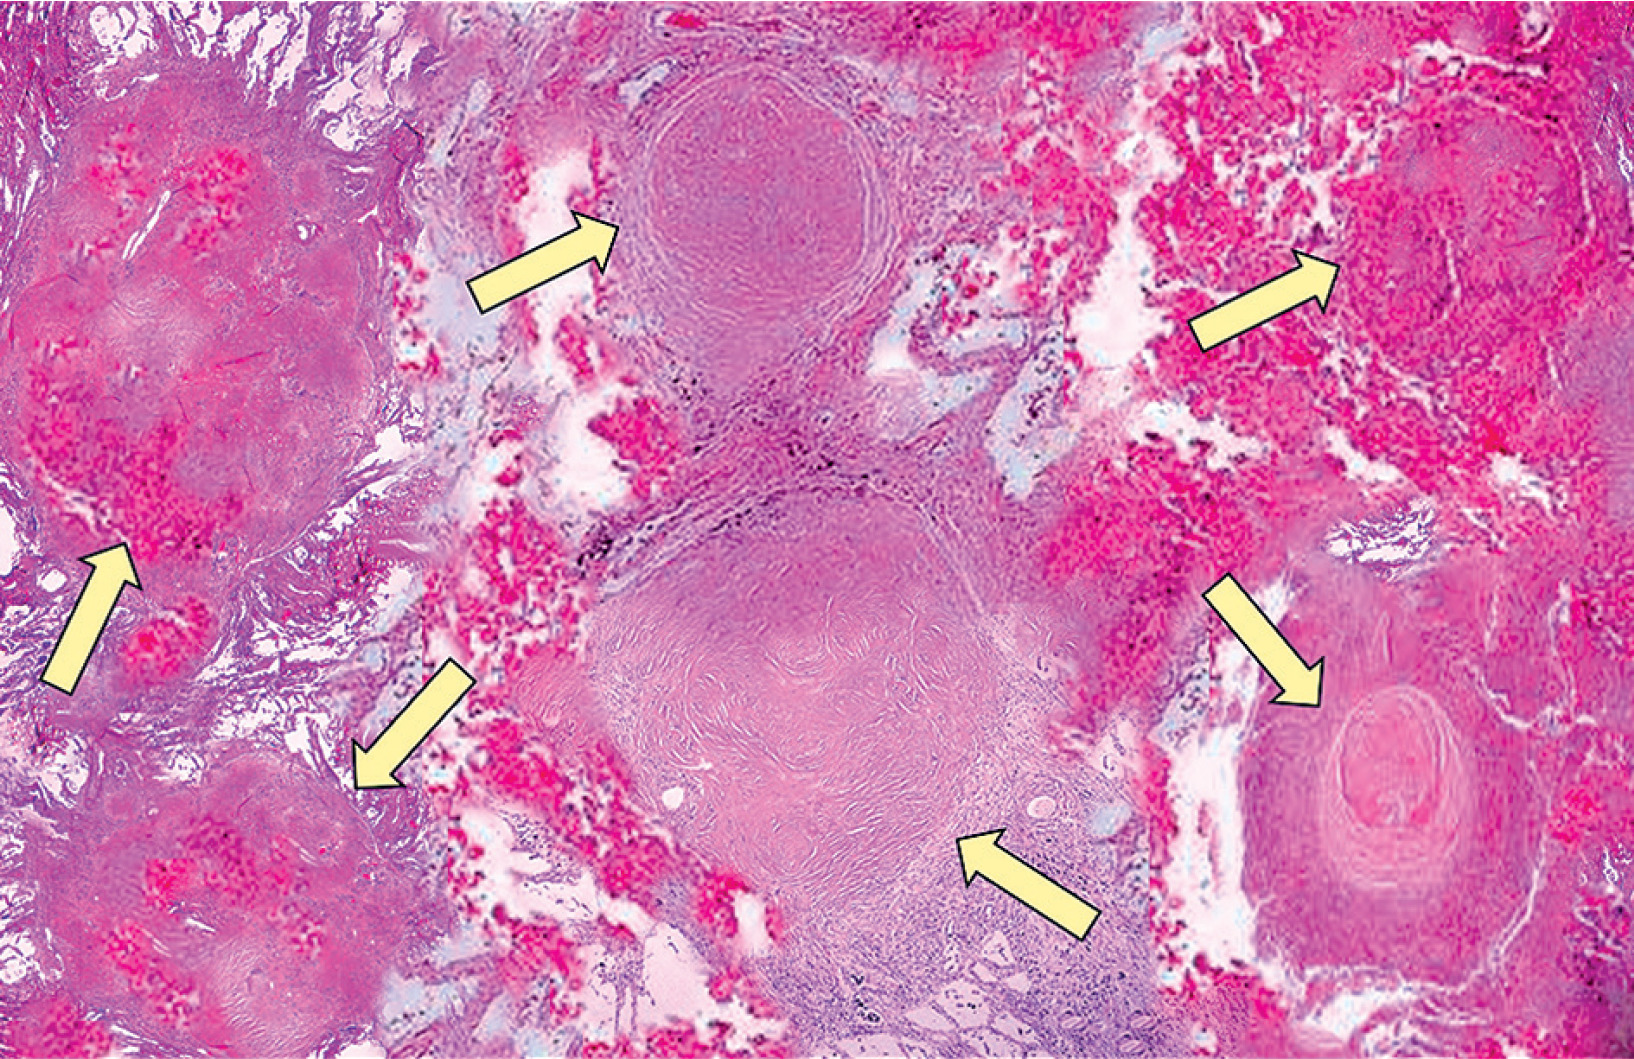

Figure 4

Histopathological appearance of lung silicosis. Silicotic nodules within the lung parenchyma (arrows), composed of interlacing bundles of dense, eosinophilic collagen with minimal associated inflammatory reaction. The number and size of silicotic nodules increase with cumulative silica exposure and duration, and correlate with the degree of restrictive lung disease